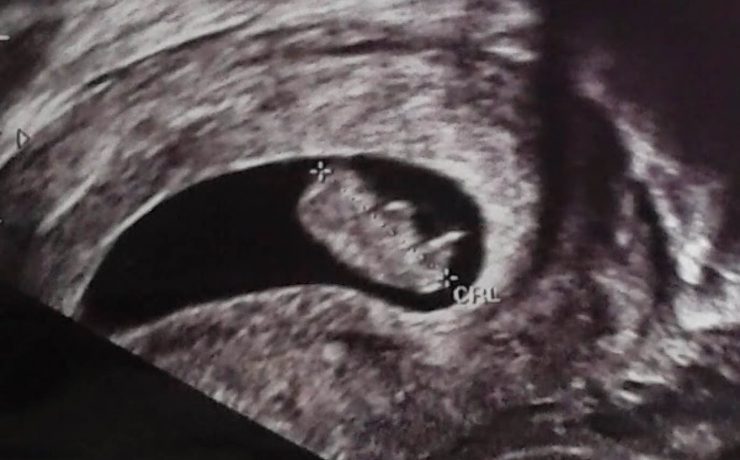

BAZO ACCESORIO SIMULANDO TUMOR SUPRARRENAL

El diagnóstico de los así llamados “incidentalomas” suprarrenales, cada vez más frecuente en la práctica clínica, plantea un diagnóstico diferencial importante. Caso clínico: Se presenta el caso clínico de una paciente de 69 años, hipertensa, con el hallazgo de una masa suprarrenal izquierda aparentemente funcionante, operada por vía laparoscópica y